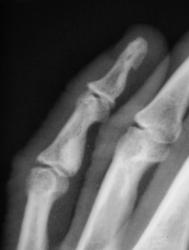

Катенёв Валенти... Дата публикации 19.06.2009, 20:43 Ваше мнение коллеги по поводу локального "уплотнения костной ткани" в средней фаланге 5 пальца левой кисти. Эностоз? Ваше мнение коллеги? Пт, 19/06/2009 - 20:46 #1 Глазков Игорь А... Не на сайте Был на сайте: 11 месяцев 3 недели назад Зарегистрирован: 19.12.2008 - 20:41 Публикации: 1597 что эностоз, но неплохо бы узнать возраст пациента. Прийди к Себе Пт, 19/06/2009 - 20:52 #2 Катенёв Валенти... Не на сайте Был на сайте: 7 лет 3 месяцев назад Зарегистрирован: 22.03.2008 - 22:15 Публикации: 54876 Пациент возраста около 30-ти лет.

Пациент возраста около 30-ти лет.